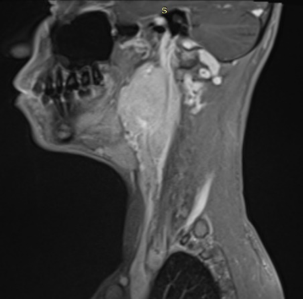

Paragangliomas are rarely seen neural crest-derived tumors. They mostly present in carotid bifurcation. %10 of cases are familial. Familial paragangliomas generally occur at a younger age and bilaterally. Paragangliomas are often slow-growing, asymptomatic cases. In patients with symptoms, swelling of the neck, dysphagia, odynophagia are most common. Physical examination of patients with carotid-based paraganglioma reveals an insensitive mass in front of SCM (fountain sign). Although they are mostly benign, they can become malignant if they make metastasize. Multidisciplinary approach is important in these patients. While the main treatment is surgery, radiotherapy can be applied in metastatic disease, inoperable patients or patients who have positive surgical margins. In this article, 2 different paranganglioma cases with lymph node metastasis are discussed. In both cases, regional radiotherapy was administered after the surgery.